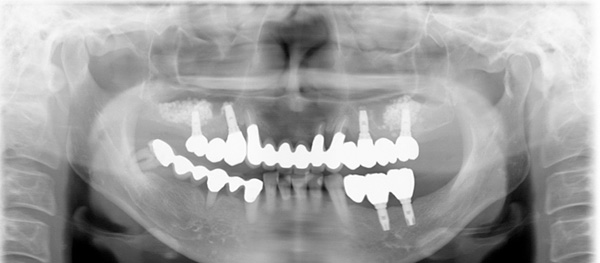

After

重度の歯周病で咬み合わせがなくなった治療は、歯周病の治療やインプラントを埋入するだけではなく、咬合診断をおこない咬合再構成が必要になってきます。